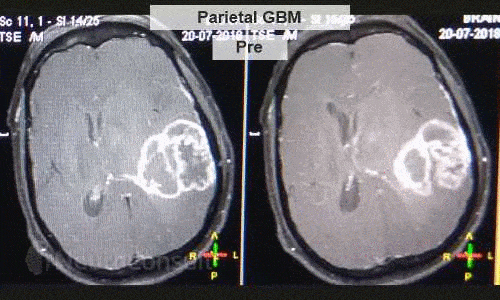

My Cases Studies & Work